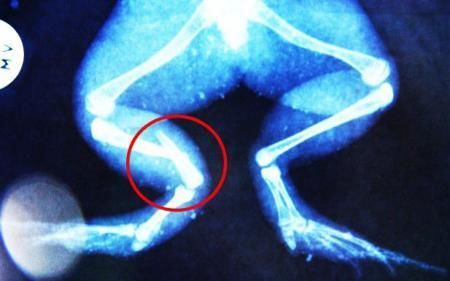

環(huán)球網(wǎng)4月2日報道 據(jù)《每日郵報》報道,上個月,南非大牛蛙布魯萊的右小腿被鄰居家的一只狗咬到,導(dǎo)致粉碎性骨折,現(xiàn)在經(jīng)過2個小時的手術(shù),它的斷腿已經(jīng)被接上,它也因此成為有史以來第一只通過外科手術(shù)用鋼針接上斷腿的青蛙。

布魯萊的主人,居住在南非約翰內(nèi)斯堡附近的62歲的安妮·米恩斯說:“我對這只青蛙如此關(guān)心,人們一定認(rèn)為我瘋了,但是我無法眼睜睜看著它那么痛苦。青蛙因其靈活的腿腳而著稱,一想到布魯萊的腿里要留下一個薄金屬片,我就感到心痛。然而我知道,如果不進(jìn)行手術(shù),布魯萊以后就沒辦法動彈了。因此我匆匆趕到獸醫(yī)那里,央求他給這只可憐的青蛙動手術(shù)。這位獸醫(yī)整天救助小貓小狗,他很難理解為什么我這么擔(dān)心一只青蛙,但是最終他還是答應(yīng)了給布魯萊做手術(shù)。手術(shù)后是幾個小時的焦急等待,我們希望它能快快蘇醒過來。不過現(xiàn)在它的傷口已經(jīng)愈合,又能在花園里跳來跳去了。X光照射顯示,它會恢復(fù)的跟以前一樣。”

野生生物專家安妮經(jīng)常為學(xué)校寫教材,她認(rèn)為這是人類第一次通過手術(shù)給一只青蛙接斷腿。在手術(shù)開始階段,獸醫(yī)把少量給狗用的麻醉藥注入到這只青蛙體內(nèi),讓它失去知覺。然后他在布魯萊的斷腿上切開一個小口,把一根小鋼針植入腿里。最后獸醫(yī)給它縫了9針,把切口縫合在一起。僅僅幾周后,布魯萊就能在安妮家附近活動了。這只青蛙大約已有25歲,主要以嚙齒動物、蛇和其他青蛙為食。布魯萊所屬的牛蛙種群正在不斷減小,目前只能在非洲南部的濕地里才能看到這種青蛙。